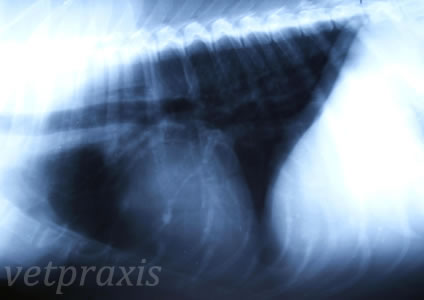

A la vista de su radiografía torácica en posición lateral derecha:

B.- Aunque el paciente sea sugerente de un problema cardiaco (raza, edad, sexo, tamaño, incluso soplo y tos seca no productiva), la radiografía me sugiere un problema respiratorio crónico, en estas condiciones la furosemida densifica la secreciones bronquiales y empeora la tos, el enalaprilo y la espironolactona aunque, probablemente, no están produciendo efectos adversos, no están ayudante a este paciente y la digoxina parece que claramente está produciendo efectos adversos digestivos y generales. Hay que retirar furosemida y digoxina, hay que usar teofilina u otro broncodilatador, hay que usar corticoides en dosis bajas unos días hasta controlar la tos y usar un tratamiento antibiótico combinado, por ejemplo, amoxicilina+ácido clavulánico y enrofloxacino durante 7-10 días.